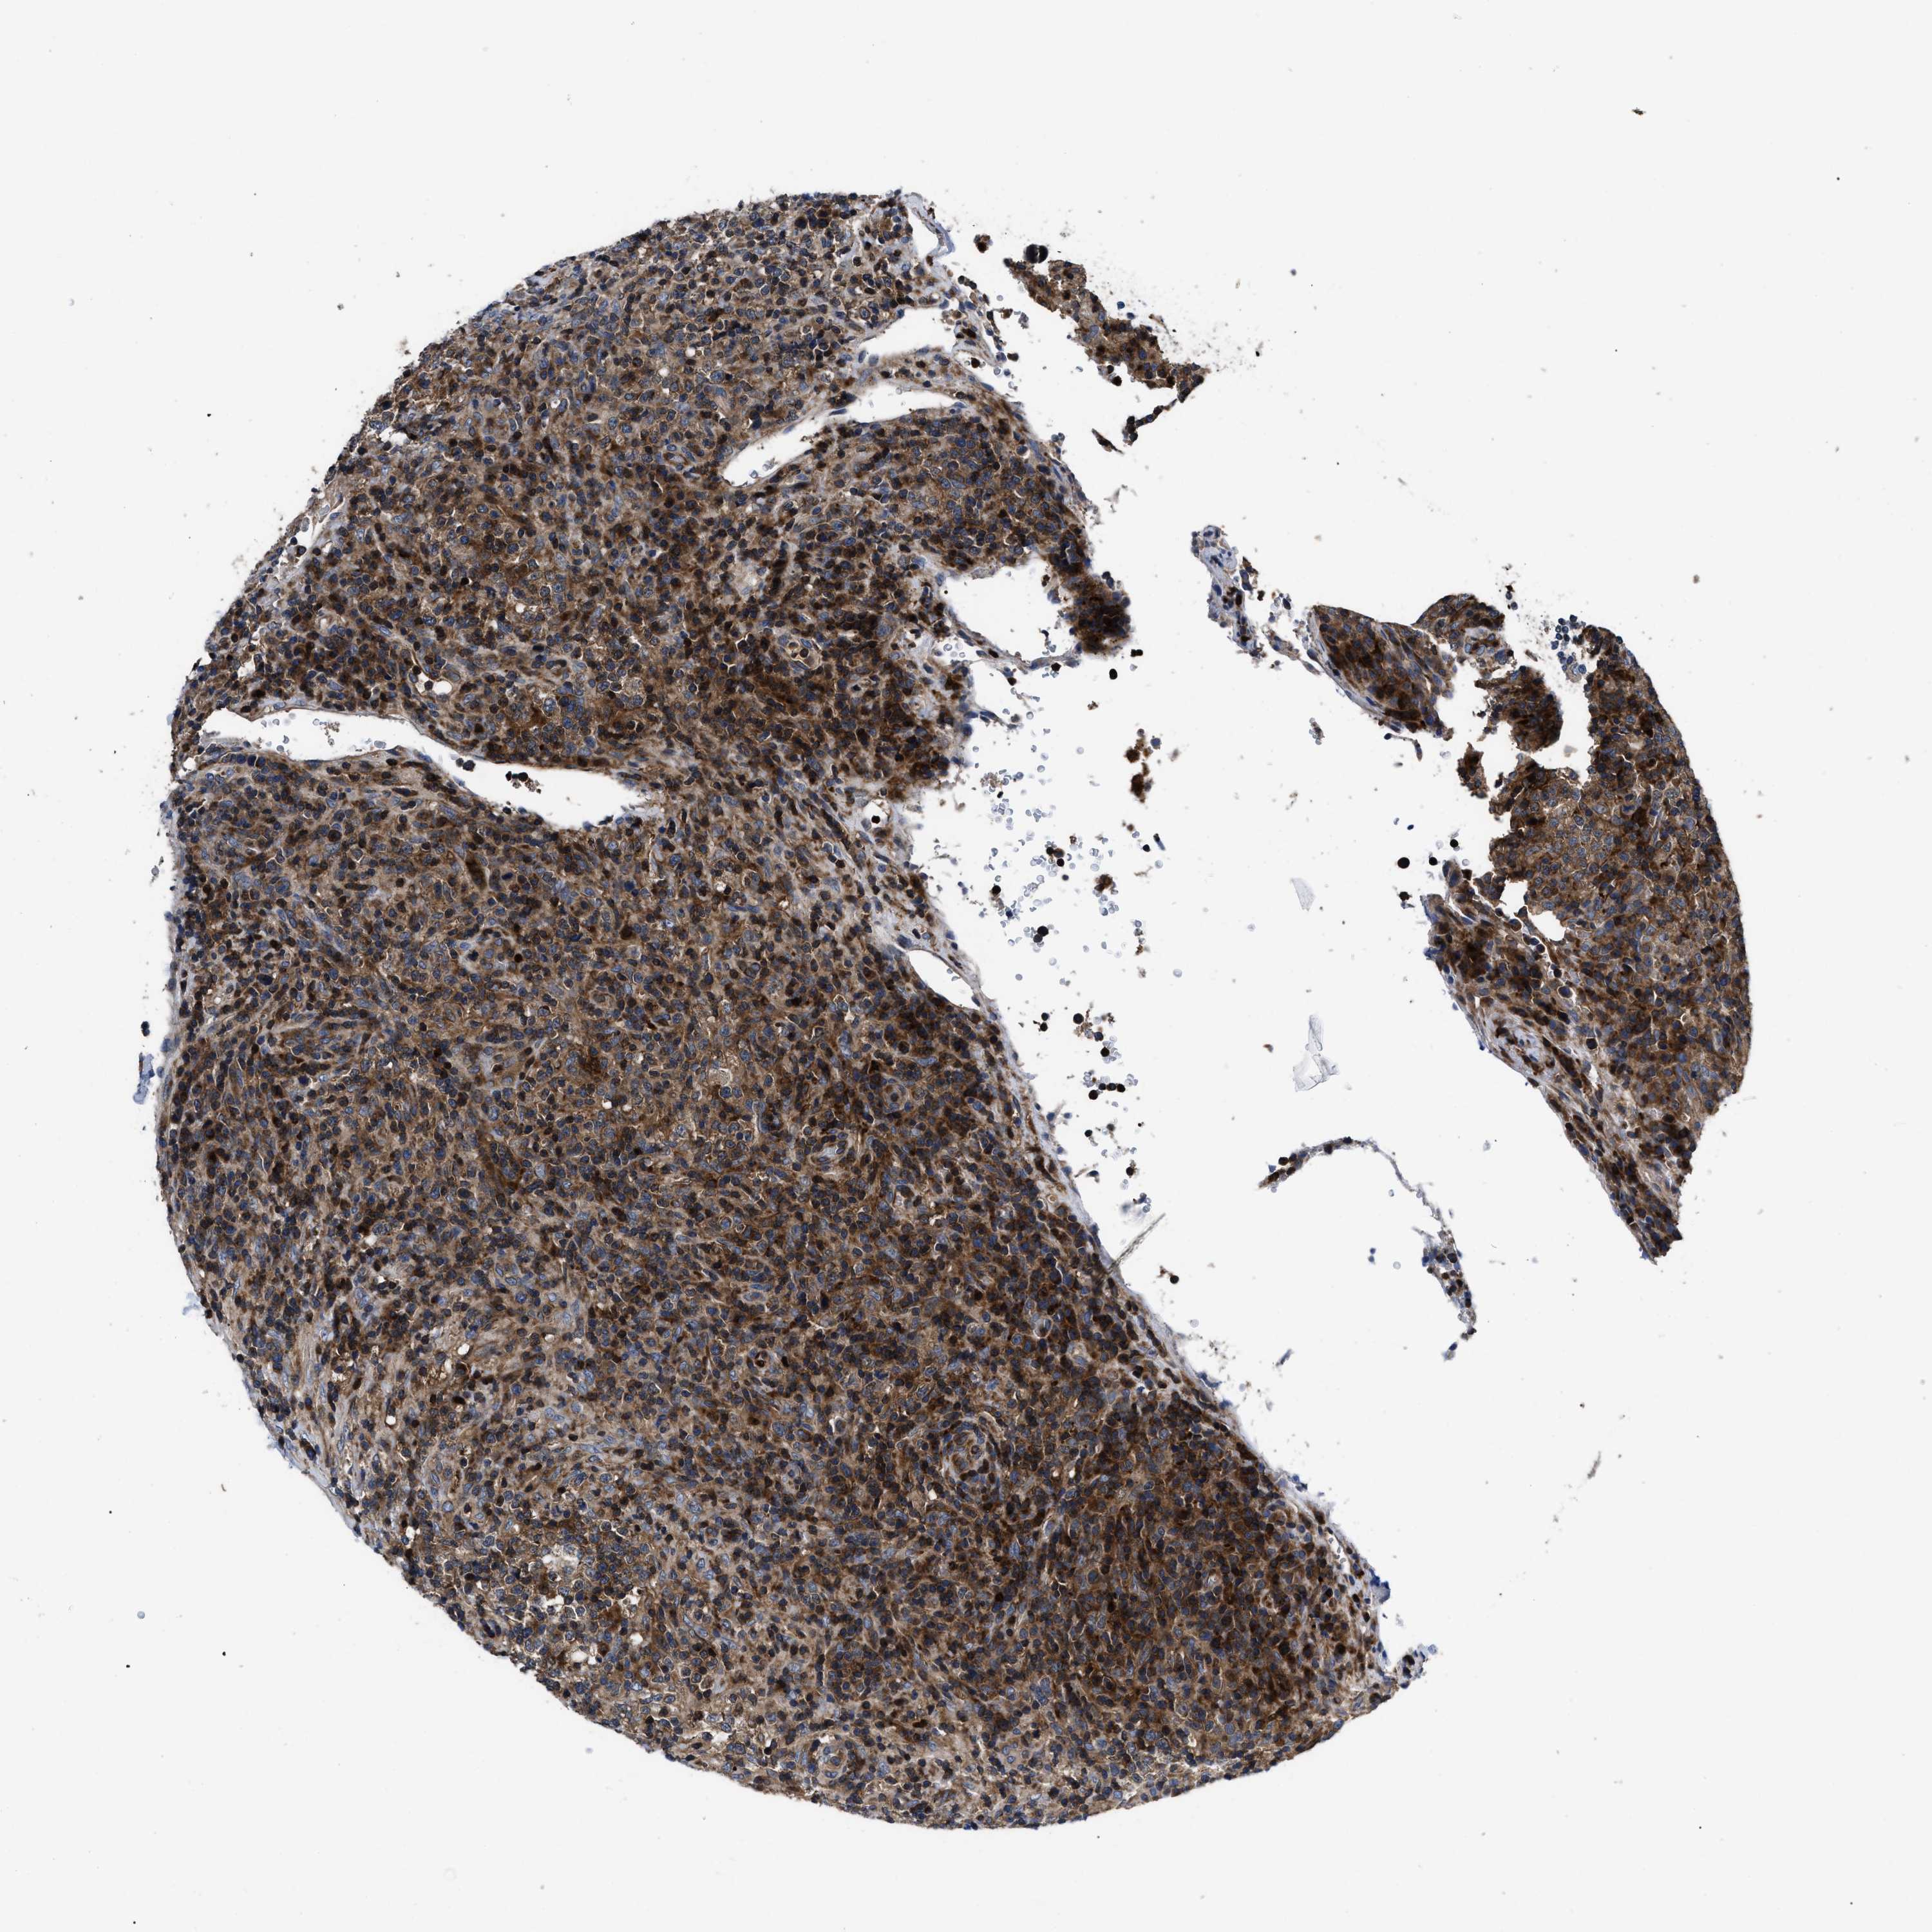

LYMPHOMA - Protein expressioni

A mouse-over function shows sample information and annotation data. Click on an image to view it in a full screen mode. Samples can be filtered based on level of antibody staining by selecting one or several of the following categories: high, medium, low and not detected. The assay and annotation is described here.

Antibody stainingi

Antibody staining in the annotated cell types in the current human tissue is reported as not detected, low, medium, or high, based on conventional immunohistochemistry profiling in selected tissues. This score is based on the combination of the staining intensity and fraction of stained cells.

Each image is clickable and will lead to virtual microscopy that enables deeper exploration of all samples and also displays staining intensity scores, fraction scores and subcellular localization as well as patient and tissue information for each sample.

Antibody HPA018162

Staining

High

Intensity

Strong

Quantity

>75%

Location

Nuclear

Cytoplasmic/membranous

Hodgkin's disease, NOS

Malignant lymphoma, non-Hodgkin's type, High grade

Malignant lymphoma, non-Hodgkin's type, Low grade